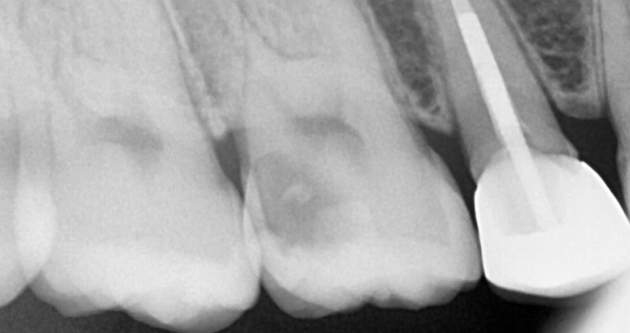

실제 사례 Before & After

바른선택치과의원은 결과로 증명합니다. 기능과 심미 모두 찾은 바른선택치과의원 실제 환자 케이스를 확인해보세요.

before Before

after After

치료 시작 전 촬영 2025.02.18 | 치료 완료 후 촬영 2025.02.28

※ 바른선택치과의원은 의료법을 준수하며 위 케이스는 실제 내원 환자분의 동의하에 공개된 사진과 동일한 환자분께 같은 조건에서 촬영한 사진을 활용했습니다.

개인에 따라 진료 및 치료 방법이 다르게 적용할 수 있으며, 효과와 부작용이 개인마다 다르게 나타날 수 있는 점을 안내해 드리며, 진료 전 전문의료진과 충분한 상담을 권해드립니다.